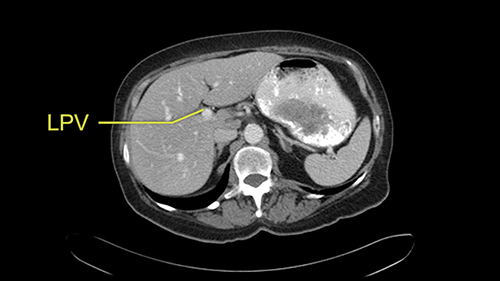

The only other most important feature that I usually consider is the portal vein split or the bifurcation, especially if doing a major liver resection like a right lobe. I like to look at the length of the common right portal vein trunk which looks like its probably long enough to put a stapler on. Final decision would be in the OR. If it wasn’t long enough and I was concerned about injuring the bifurcation or the left portal vein, then I would divide the Segment 5-8 and 6-7 portal tracks individually.

![[LPV]](jpg/preop_sg_moment4b.jpg)

This patient has an interesting minor anomaly with what looks like a Segment 7 portal vein coming off close to the bifurcation of the right portal vein but again if I was doing a right lobe which is my plan, this wouldn’t be an issue.